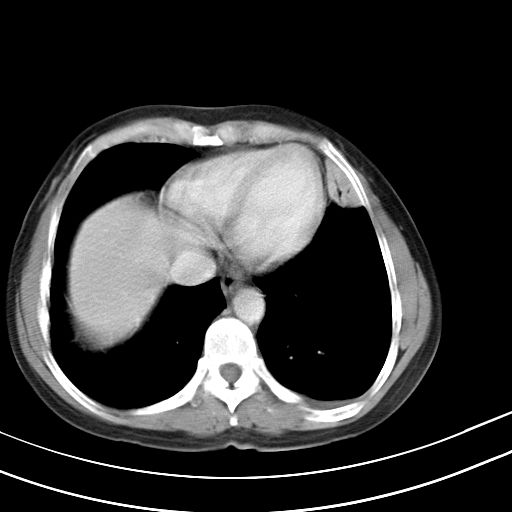

女,47岁,咳嗽胸痛一个星期,我们考虑肺结核,左下肺病灶肿瘤像不像,请高手指点。急。

右肺考虑炎症,建议抗炎后复查,左肺下叶考虑肺不张。

考虑两肺炎症,左胸腔积液,建议治疗后复查!

考虑炎性病变,左肺舌叶病灶需要与早期肺脓肿鉴别(结合实验室),左侧少量胸腔积液。

考虑两肺炎症,建议治疗后复查,左侧少量胸腔积液

1)右肺上叶前段及左肺上叶舌段感染性病变;建议抗炎治疗后复查。2)左侧少量胸腔积液。